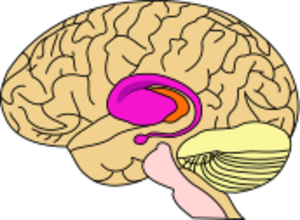

مرض هنتنجتونHuntington's disease هو اضطراب وراثي شديد في الجهاز العصبي. ويتسبب هذا المرض في تدمير خلايا الدماغ، كما يتسبب في حدوث حركات لا إرادية للجسم إلى جانب اضطراب عقلي تعقبه الوفاة. وهذا الاضطراب يصيب الناس من كلا الجنسين بصرف النظر عن العرق البشري. وأخذ هذا المرض اسمه من اسم أول من اكتشفه وهو جورج هنتنجتون الطبيب الأمريكي الذي كان أول من وصف هذا المرض في عام 1872م. وكانت هذه الحالة أصلا تسمى رَقَاص هنتنجتون.

الآلية

التغيرات الخلوية بسبب mHTT

التغيرات الكبرى بسبب mHTT